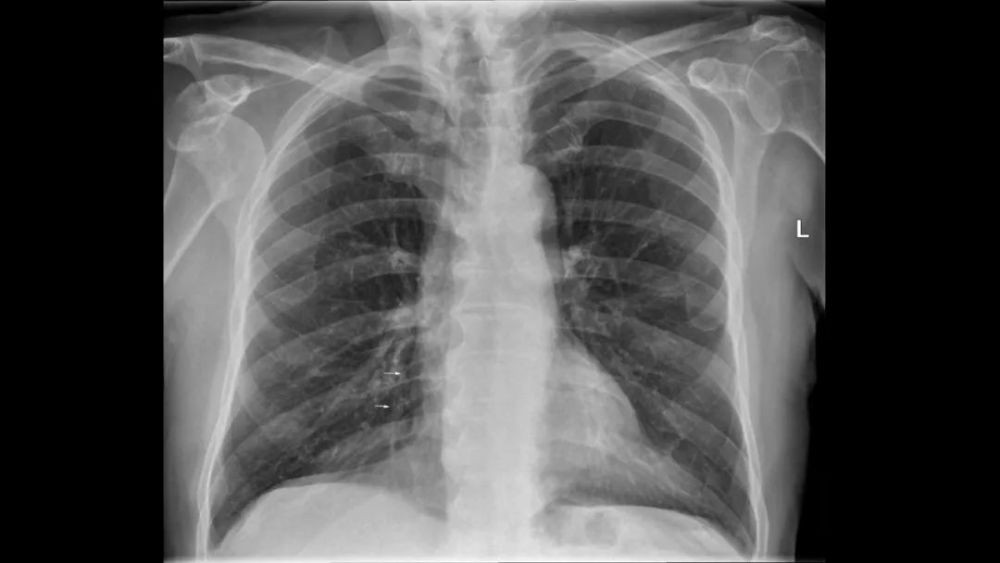

左侧水平裂

Left minor fissure

CT上的检出率为:8% , AP胸片为1.6%

左侧水平裂将舌叶从下叶其它部分分隔出来 舌叶仍然保留其上段和下段 , 不同于右肺中叶 内侧段和外侧段 , 因此左肺的段解剖保持完整